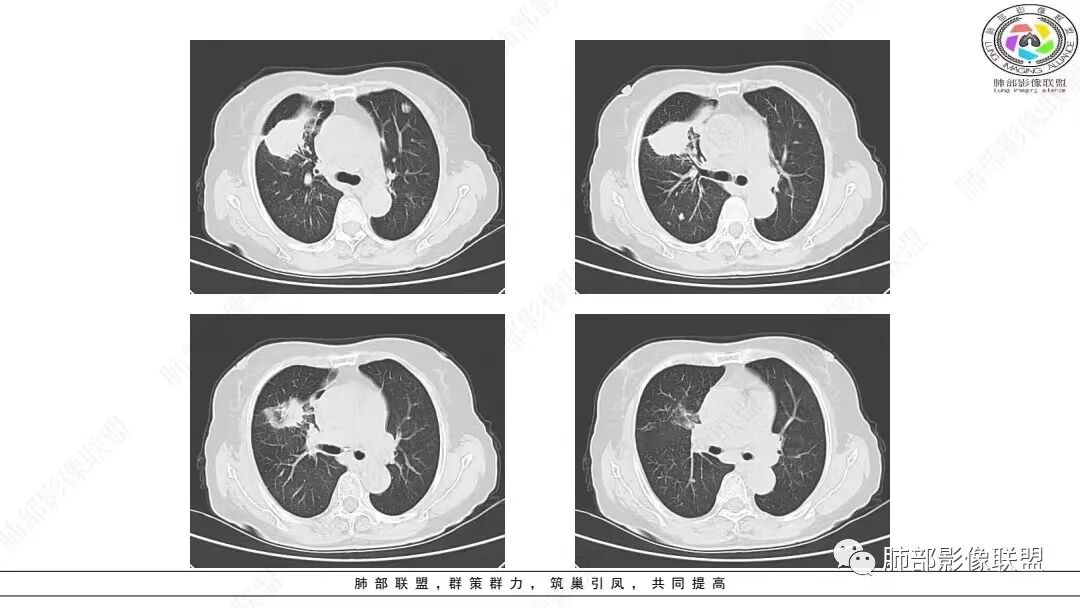

2.影像学特点:右肺上叶前段胸膜下不规则较大团块影,边界清楚欠光整,浅分叶,肺血管支气管出入,边缘膨隆胸膜凹陷具有一定张力,未见典型粗短毛刺,部分围以边界清楚的磨玻璃影,灶周小叶间隔增厚。块影密度不均,渐进性强化,可见砂砾样钙化,未见明显液化坏死或空洞。增强后病灶显示渐进性强化。MIP显示病灶内肺动脉穿行、并部分肺动脉受侵变细。纵隔及右锁骨上(胸廓入口)见肿大淋巴结。两肺可见多发大小不一的结节影,边界清楚,随机分布。

胸椎体溶骨性吸收破坏,突破骨皮质。腹部扫描未见肿块影。

3.总结:老年女性。无明显呼吸系统临床症状。实验室检查未见明显异常。右肺上叶前段团块➕右侧颈部、纵隔淋巴结肿大➕两肺多发结节。符合恶性病变。

病灶较大较光整,支气管出入,缀以边界清楚磨玻璃影,有一定张力,不均匀强化,疑及肺腺癌或者大细胞肺癌都在情理之中。双肺多发病灶,符合转移瘤特征。     注意胸椎体溶骨性吸收破坏,突破骨皮质,经验上这样的改变更支持转移而不支持淋巴类肿瘤。